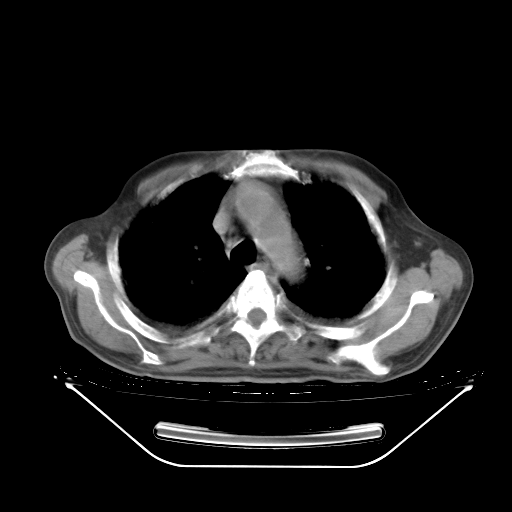

今天复查肺部CT,发现双肺广泛磨玻璃样改变。所以我把3月19日和5月9日相隔50天的肺部CT上传。请大家会诊。

5月9日肺部CT(在4月27日齐鲁医院肺部CT描述部分肺组织磨玻璃样改变,12天后肺组织广泛磨玻璃样改变)

2009年5月9日肺部CT